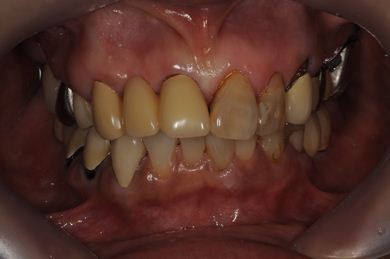

治療前

• 治療前